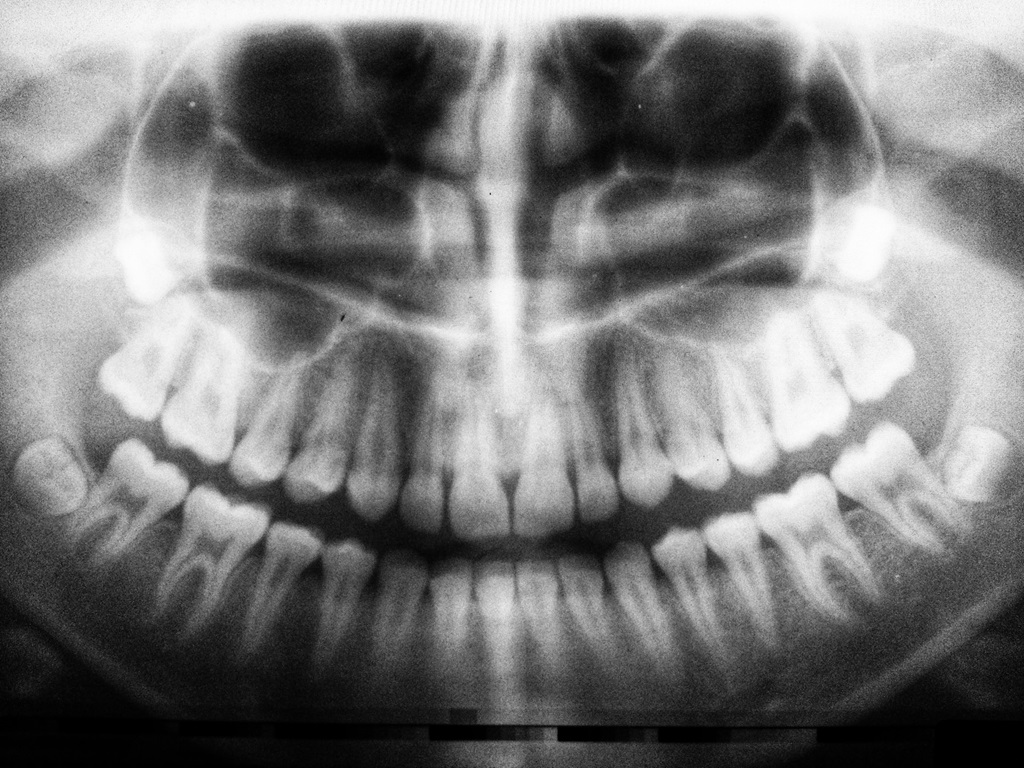

Panoramic Radiograph (OPC, OPT) image of wisdom teeth left behind in eruption, which are considered dental foci

A multitude of factors can contribute to the formation of these elusive dental foci. From tooth decay and flawed root canal fillings to inflammation around implants, lingering infected root fragments, damaged teeth, impacted teeth, and untreated periodontal disease – each plays a role in the development of these hidden infections.

- Partial or fully unerupted teeth (impacted teeth).